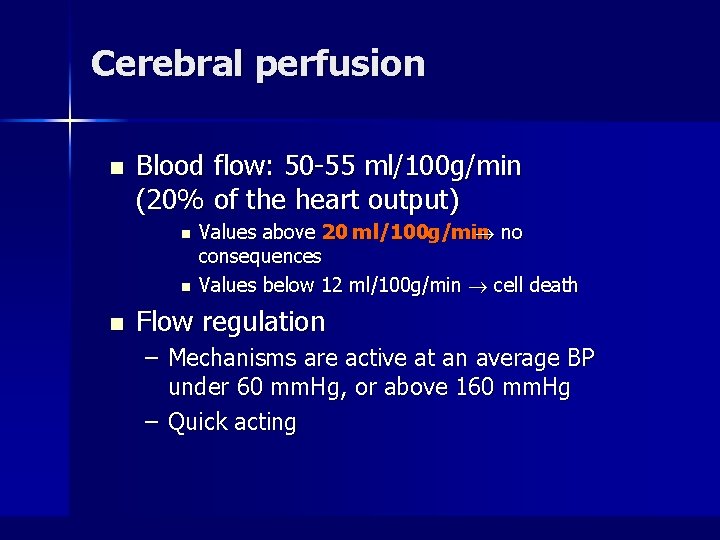

Cerebral perfusion n Blood flow: 50 -55 ml/100 g/min (20% of the heart output) n n n Values above 20 ml/100 g/min no consequences Values below 12 ml/100 g/min cell death Flow regulation – Mechanisms are active at an average BP under 60 mm. Hg, or above 160 mm. Hg – Quick acting